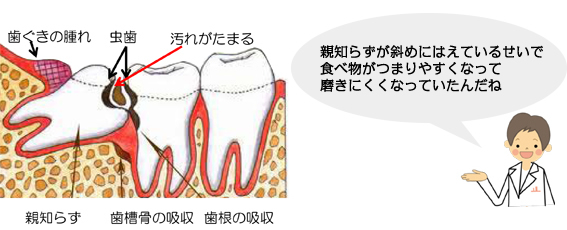

隣の歯が虫歯になりやすくなります!

このような生え方の親知らずは前の歯に当たっていて、これ以上生えてくる事はありません!

周期的に歯茎が腫れたり、顎が痛くなったり、体調が悪い時・疲れがたまっている時に諸症状がでます。

放置しておくと、前の歯が根元付近で虫歯になり神経をとらないといけなくなったり、最悪抜歯になる事もあります!

この状態の親知らずが生えている方は早めに抜歯をお勧めします。